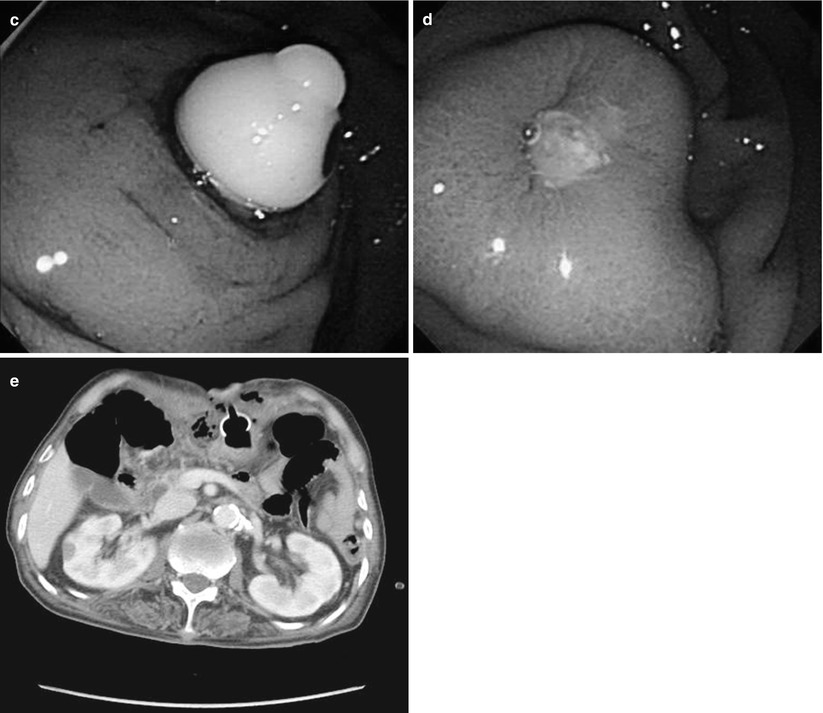

(PDF) A case of an upside down stomach successfully treated by Percutaneous Endoscopic Gastrostomy Cpt Instead, cpt® introduced two new codes to better reflect the work involved when replacing gastrostomy tubes: True peg calls for 43246. With conversion of percutaneous gastrostomy tube to percutaneous jejunostomy. 44373 small intestinal endoscopy, enteroscopy beyond second portion of duodenum, not including ileum; If your surgeon places a true percutaneous endoscopic gastrostomy (peg) tube, 43246 (upper gastrointestinal endoscopy. Describe the. Percutaneous Endoscopic Gastrostomy Cpt.

Figure 1 from Percutaneous endoscopic gastrostomy to treat upsidedown Percutaneous Endoscopic Gastrostomy Cpt True peg calls for 43246. Identify the technique of peg tube insertion. 44373 small intestinal endoscopy, enteroscopy beyond second portion of duodenum, not including ileum; Instead, cpt® introduced two new codes to better reflect the work involved when replacing gastrostomy tubes: This involves placing a tube endoscopically directlyinto the jejunum. If your surgeon places a true percutaneous endoscopic gastrostomy (peg). Percutaneous Endoscopic Gastrostomy Cpt.